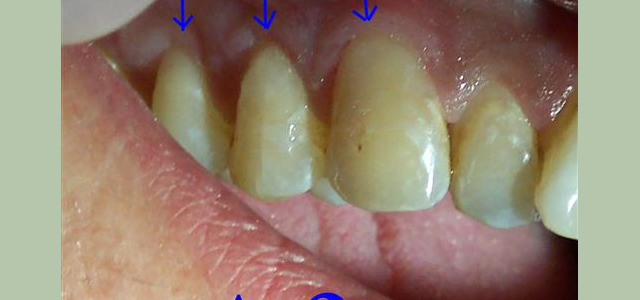

Our preventive dentistry services focus on preventing dental problems through regular visits for routine exams and cleanings. By coming to our office every six months for visits, it helps us monitor any changes in your dental health and make suggestions for how to improve your at-home dental hygiene routines. It is our goal to prevent small issues from developing into larger problems. Our preventive dentistry services include:

Checkups & Cleanings • Oral Cancer Screenings • TMJ Treatment/Appliances • Gum Disease Treatments • Bruxism Appliances